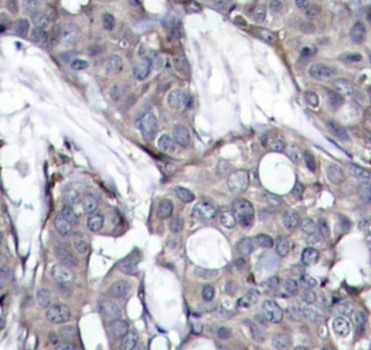

• AP0237: image 2

Immunohistochemical analysis of paraffin-embedded human breast carcinoma tissue using Phospho-HSPB1-S82 antibody.